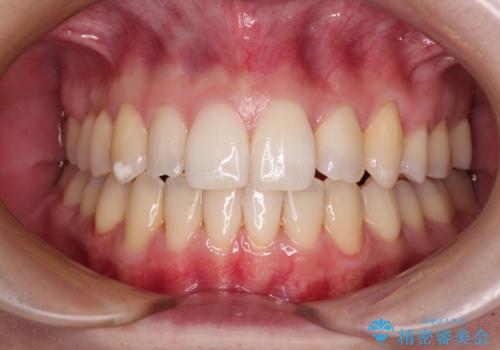

[ ディープバイト ] 深い噛み合わせの改善 マウスピース矯正

![[ ディープバイト ] 深い噛み合わせの改善 マウスピース矯正の症例 治療前](https://seimitsushinbi.jp/wp/wp-content/uploads/2022/03/dc9c092565b160bca6dd53d63f6aeffb-500x350.jpg?v=1646893459)

![[ ディープバイト ] 深い噛み合わせの改善 マウスピース矯正の症例 治療後](https://seimitsushinbi.jp/wp/wp-content/uploads/2022/03/5f1b12b750c3b8c04cdc49e53bc8f89d-500x350.jpg?v=1646893434)